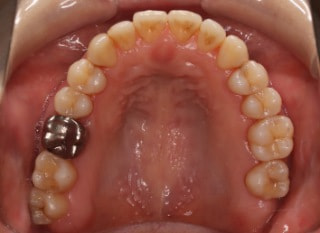

検査時パノラマレントゲン

全体の歯根のパラレリング(平行性)は悪い状態ではありません。顎関節の変形などはありません。鼻閉もありません。

成人の反対咬合なので、少し顎関節にダメージはありますが、重症ではありません。CO(中心咬合位)の位置には問題があります。CO-CRのズレが存在しますので、顎関節には負担がかかっています。